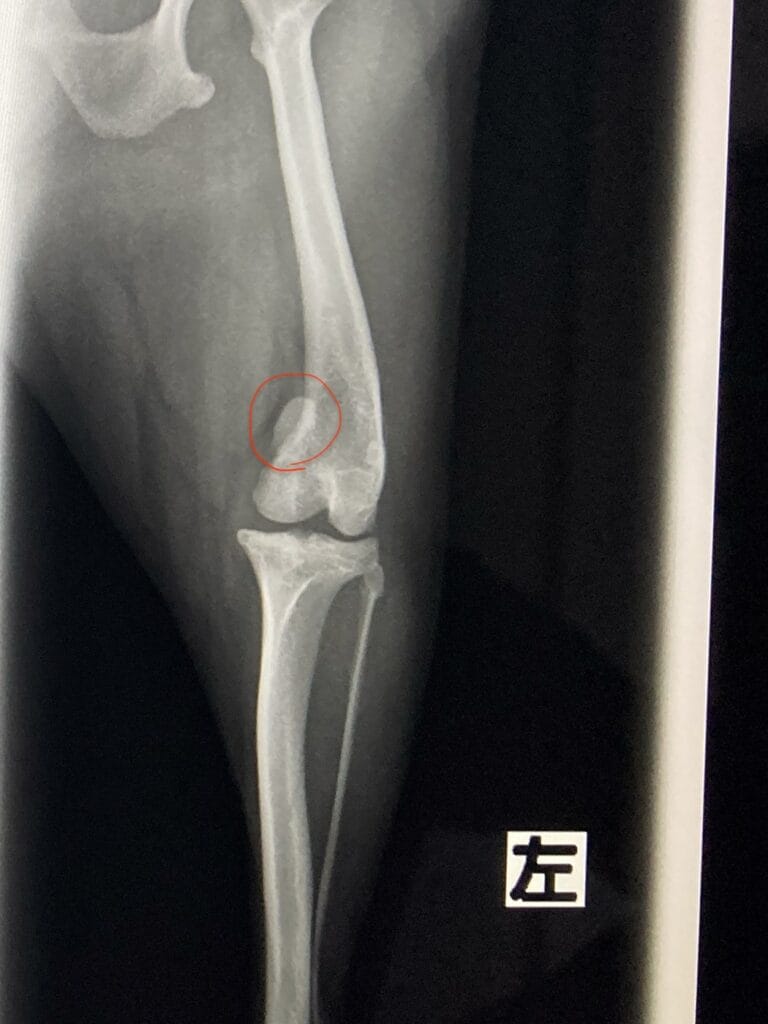

整形外科的検査とレントゲン検査の結果、左側の前十字靱帯断裂とパテラグレード4と診断しました。

前十字靭帯とは

膝関節内で大腿骨(太ももの骨)と脛骨(すねの骨)を結ぶ太い靱帯があり、脛骨(すねの骨)が前方に移動するのを防ぎ、膝関節を安定させる働きをしています。

前十字靭帯が断裂すると脛骨(すねの骨)が前方に移動し、歩く際に支える力がなくなってしまい、そのため違和感などで片足歩行になる傾向があります。

パテラグレード4とは

膝蓋骨が常に脱臼しており、手で押しても元に戻らない状態です。

前面からの撮影